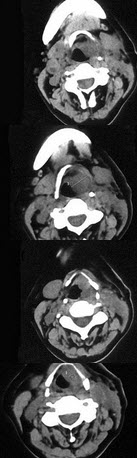

女,54岁,鼻咽部异物感约3个月,PE://左侧声带固定,可见肿物,CT如图所示,应诊断为()

A、喉部乳头状瘤

B、喉癌

C、喉部血管瘤

D、慢性增生性喉炎

E、增生型喉结核

B